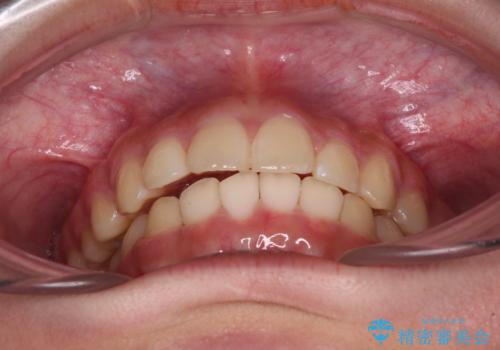

下の前歯が隠れてしまうほど深い咬み合わせ 高校生のインビザライン矯正治療

- 前歯の叢生と深い咬み合わせを気にして来院された患者様です。

奥歯の咬み合わせを見ると、上顎が下顎に対して相対的に前方にありました。